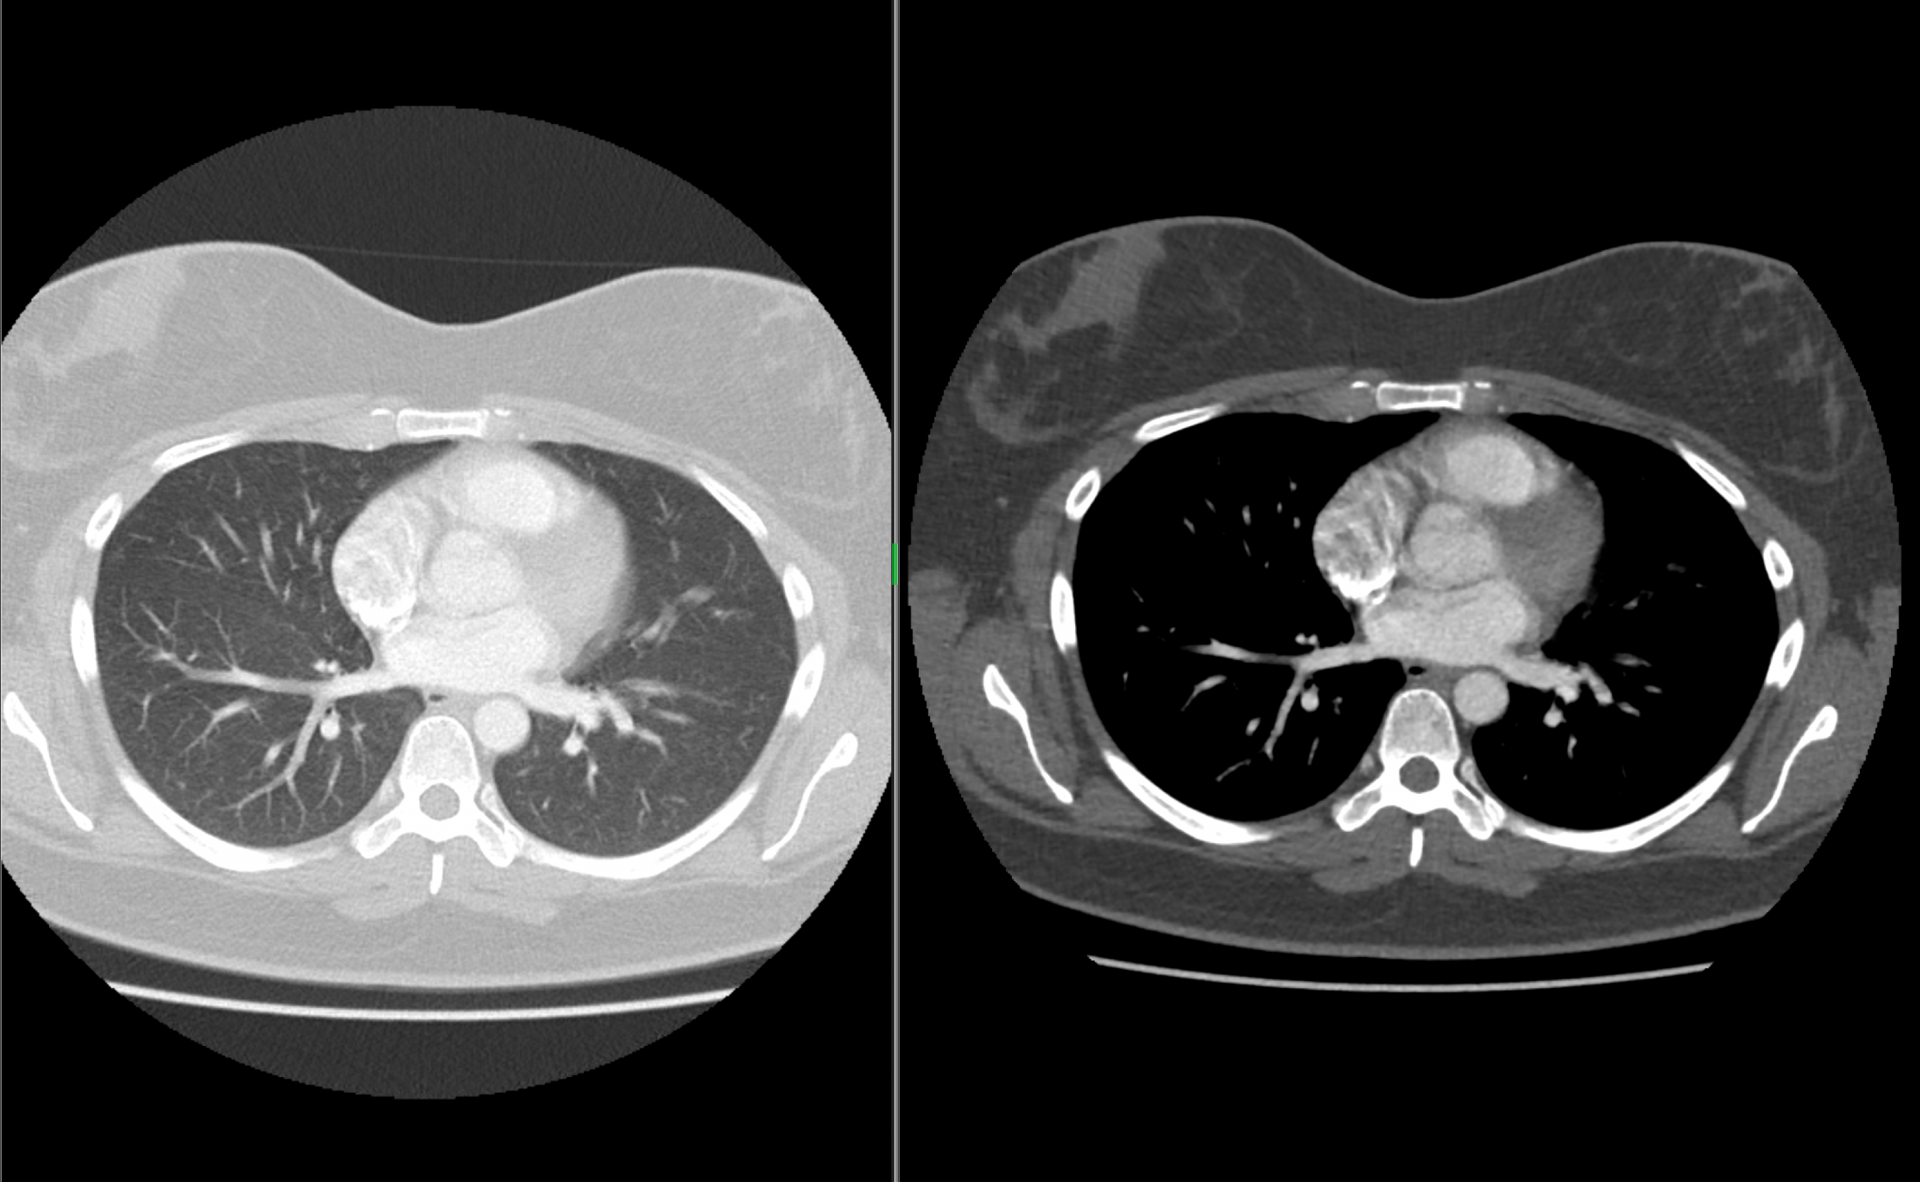

Ukázky snímků